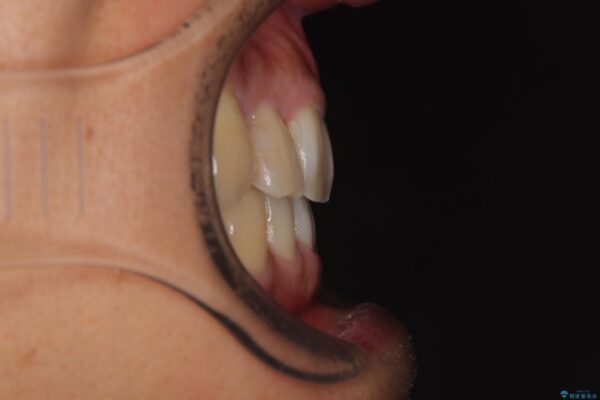

「八重歯を治したい」とご相談いただいた患者様の症例をご紹介します。

上下の前歯部に強い叢生(ガタガタの歯並び)があり、そのまま歯を並べると出っ歯になってしまう可能性がありました。

治療前

• 八重歯と前歯のガタガタを抜歯矯正で治療|クリアブラケット使用例 治療前画像